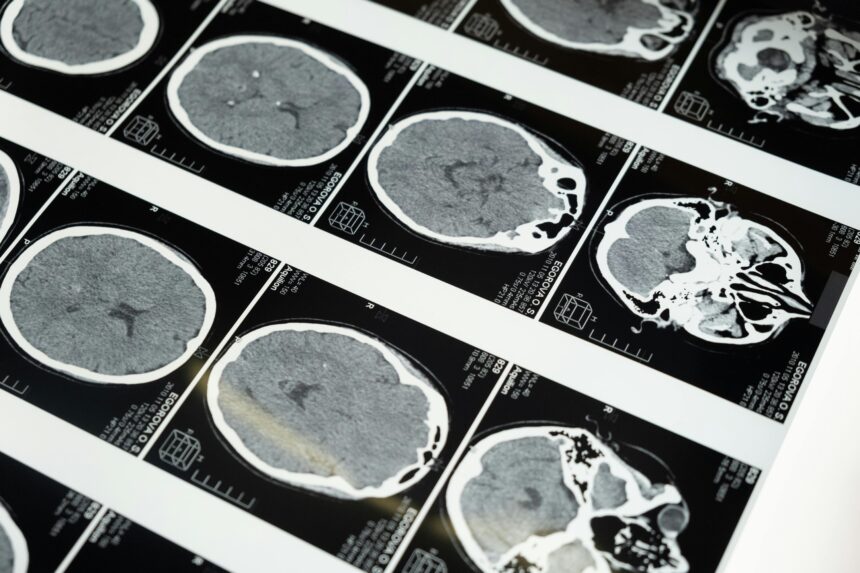

Doenças priônicas afetam o cérebro. São raras, mas perigosas.

cottonbro studio/Pexels